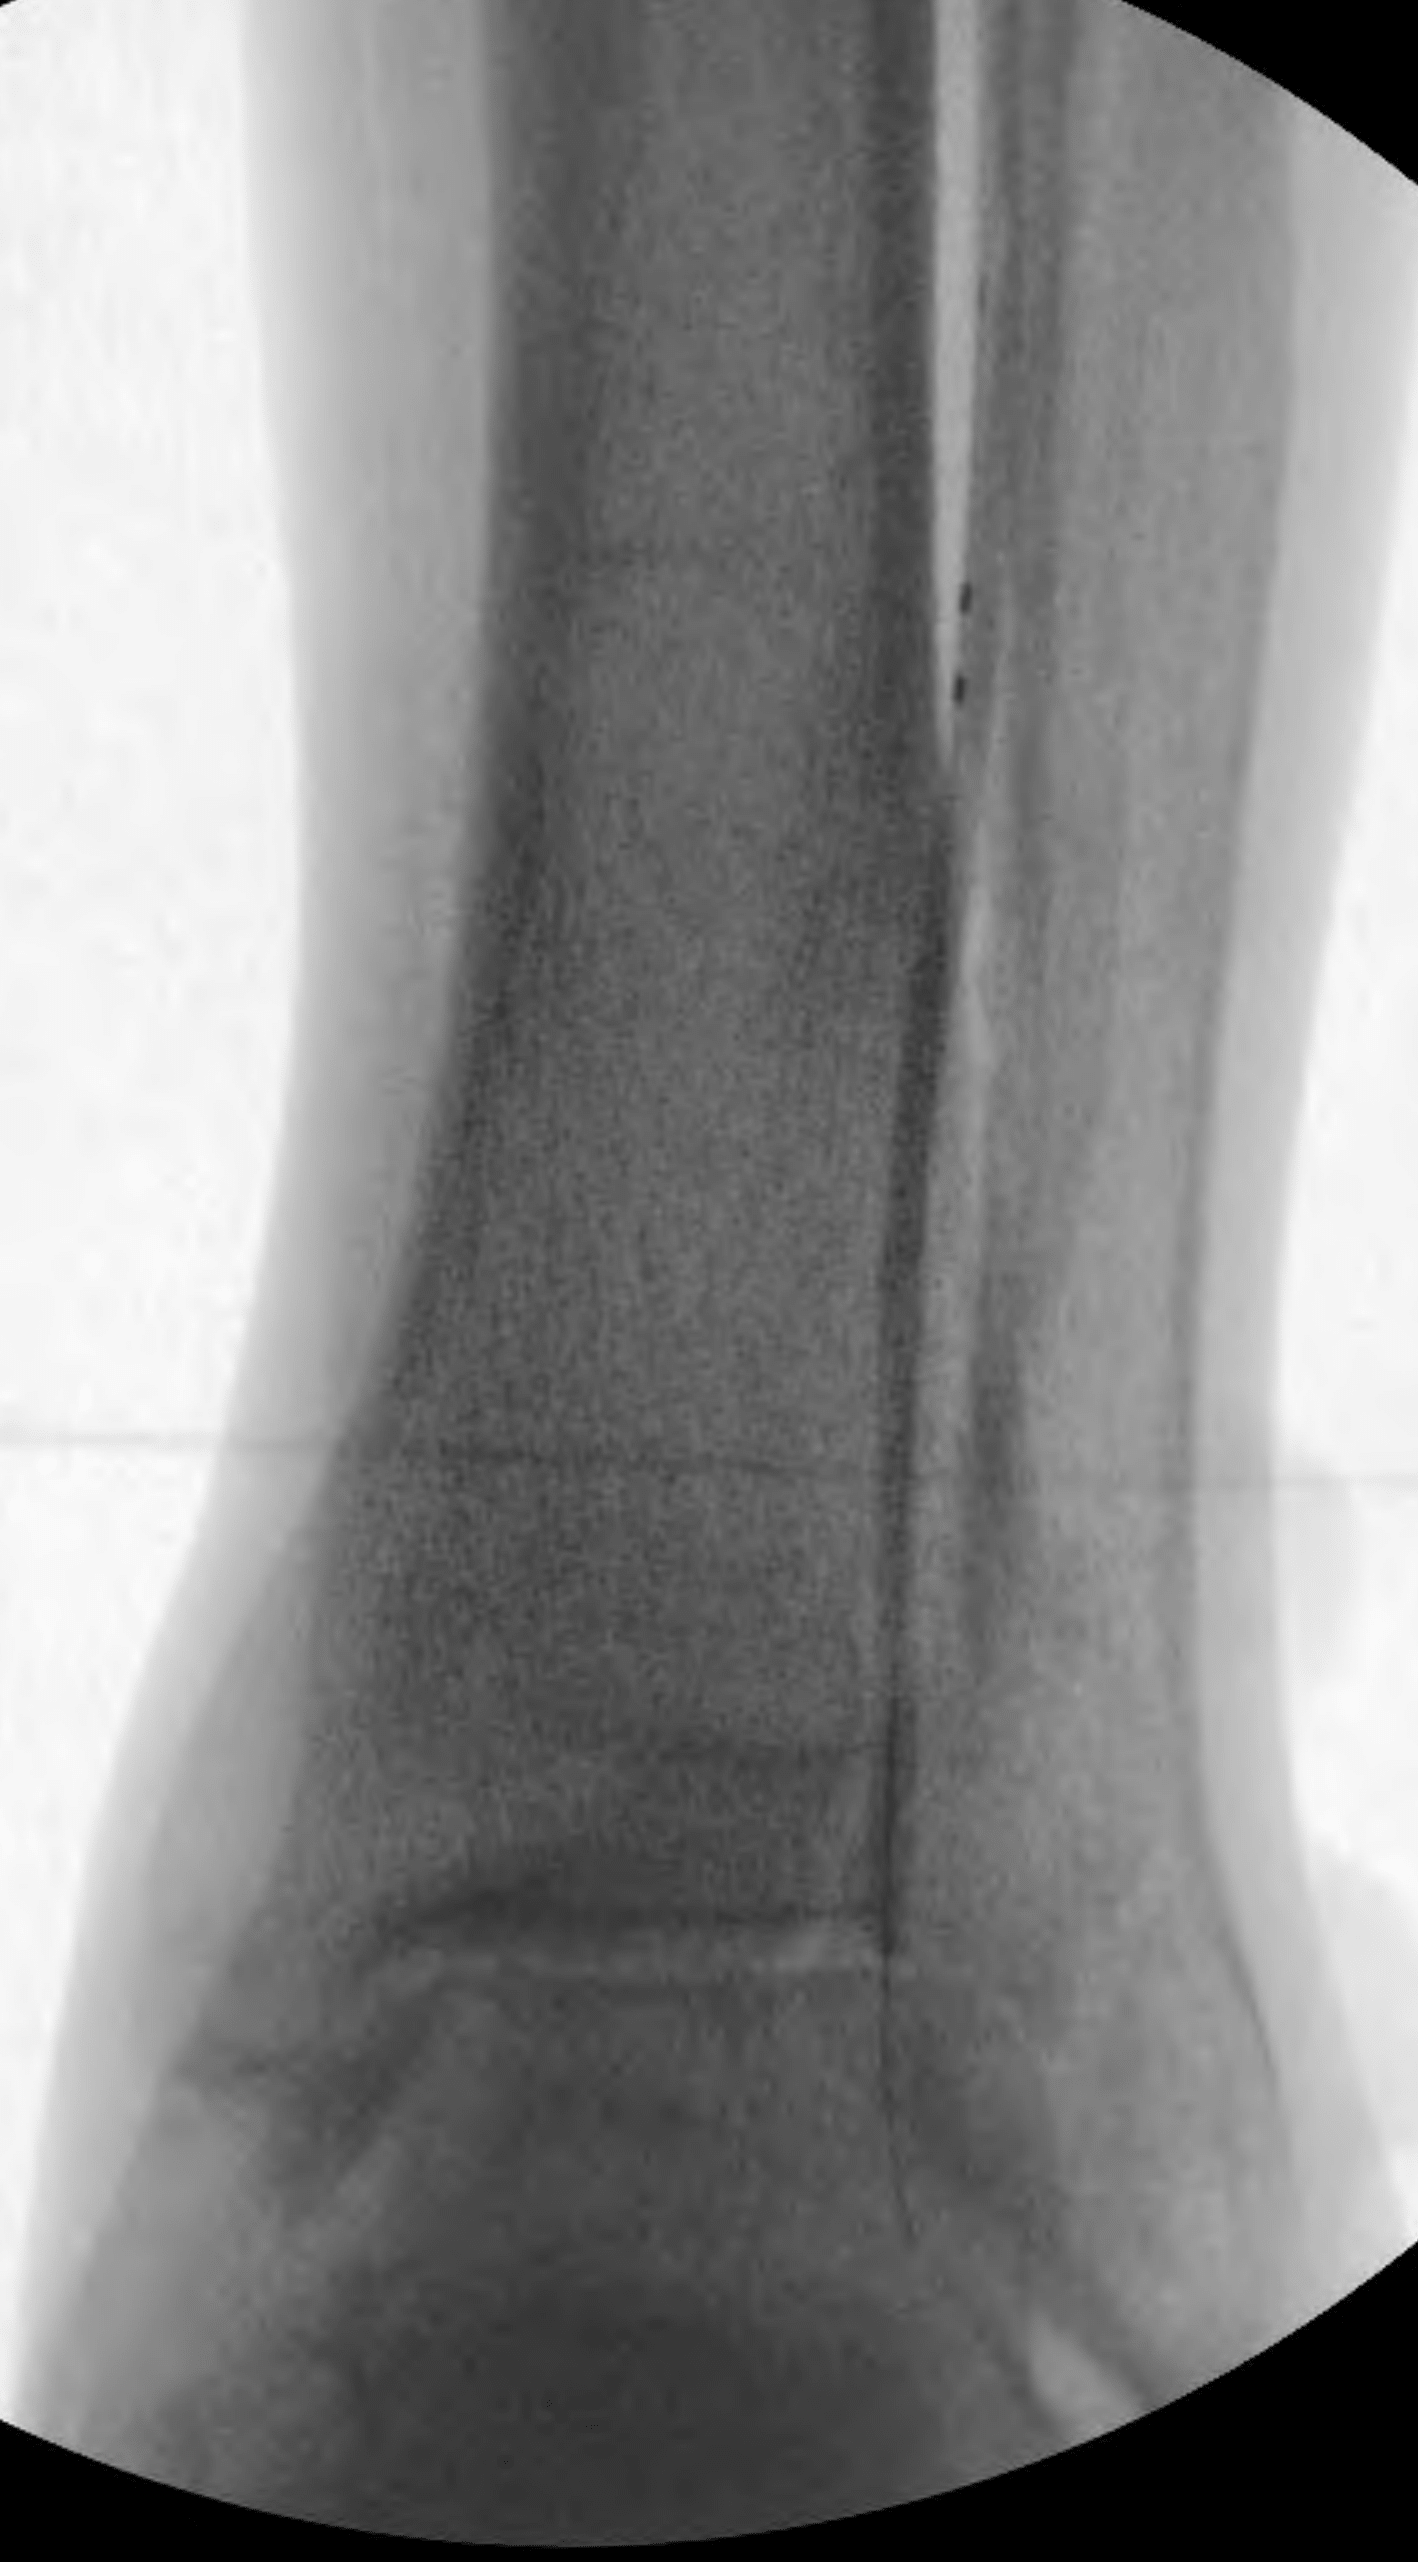

This allowed advancement of the antegrade wire (from the “up and over” access) across the occlusion in the far-distal anterior tibial artery into the dorsalis pedis artery. This was achieved carefully under extravascular ultrasound visualization. Next, completion angioplasty was performed with a 3-mm angioplasty balloon across the entirety of the distal anterior tibial artery occlusion into the patent dorsalis pedis artery (Figure 10).

The anterior tibial artery was successfully recanalized, with robust flow established into the dorsalis pedis artery (Figures 11 and 12). The patient tolerated the procedure well and did not have any complications. At 4 weeks post-intervention, the patient’s ulcer had significantly reduced in size/depth and was almost healed.